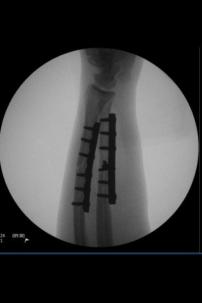

Here’s why: last summer, my brother Justin, actually was in a hit-and-run accident while riding his bike not too far from this intersection and literally broke his arm in half. Now I’m squeamish, but Justin seems fairly entertained by his wounds, so I’ve included some photos.

Truly, what Justin seemed most disappointed about was not being able to ride his new bike with a cast, not being able to write (just his luck, it was his left hand and he’s left handed), and not being able to kayak, or do yoga or go in the pool until his stitches healed. Sure, once he realized how difficult it would be the first couple weeks to get dressed, and shower, and be independent, his frustration increased, but that only lasted a couple of days and never manifested into anger. Eventually he just started wrapping a plastic bag around his arm when in the pool and kayaking, and simply figured out how to do pretty much everything he wanted to just differently than before.

So how is it that one person gets honked at and goes from 0-100 in a second, and the other gets hit by a car, has surgery, endures pain, endless medical bills, will forever have metal plates his arm, life changes etc., yet only experienced moments of frustration?